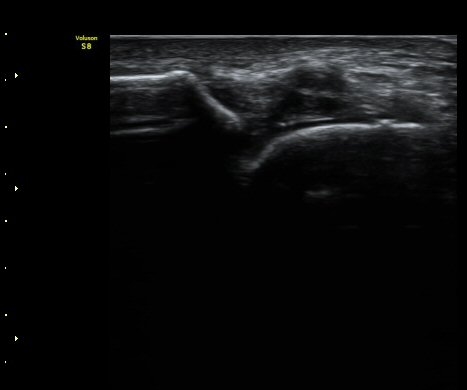

¹ß¸ñ°üÀý ¾Õ Á¾´Ü¸é°Ë»ç¿¡¼­ ¼Ò·®ÀÇ ¼ö¾×Àú·ù°¡ °üÂûµÈ´Ù(±×¸² 1, 2).